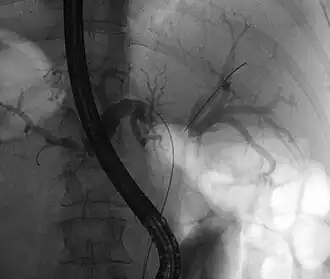

![]() опухоль Клатскина во время РХПГ. В левом и правом желчных путях. В обе половины вводили трубку с контрастом. в области слияния хорошо виден недостаток контраста. | |